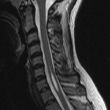

Syringeomelie